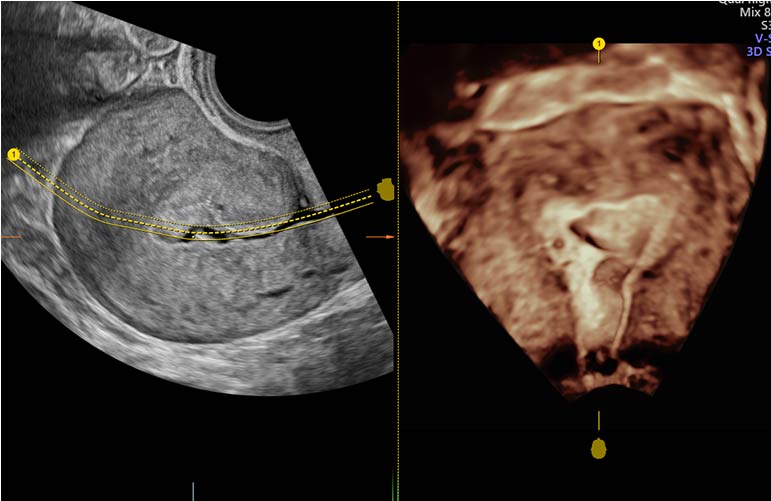

The majority of ultrasounds for fertility testing and treatment are performed transvaginally (via the vagina) with a thin specialized wand. The ultrasounds are not painful, but they are slightly unpleasant.

Ultrasound scans can provide information on the ovaries, endometrial lining, and uterus during infertility testing. Specialized ultrasounds can be used to assess ovarian reserves, uterine shape, and whether the fallopian tubes are open or blocked in greater detail.

Ultrasound is used during fertility treatment to monitor follicle development in the ovaries and the thickness of the endometrial lining. During IVF, ultrasound is also used to guide the needle through the vaginal wall to the ovaries. During embryo transfer, some doctors use ultrasound.